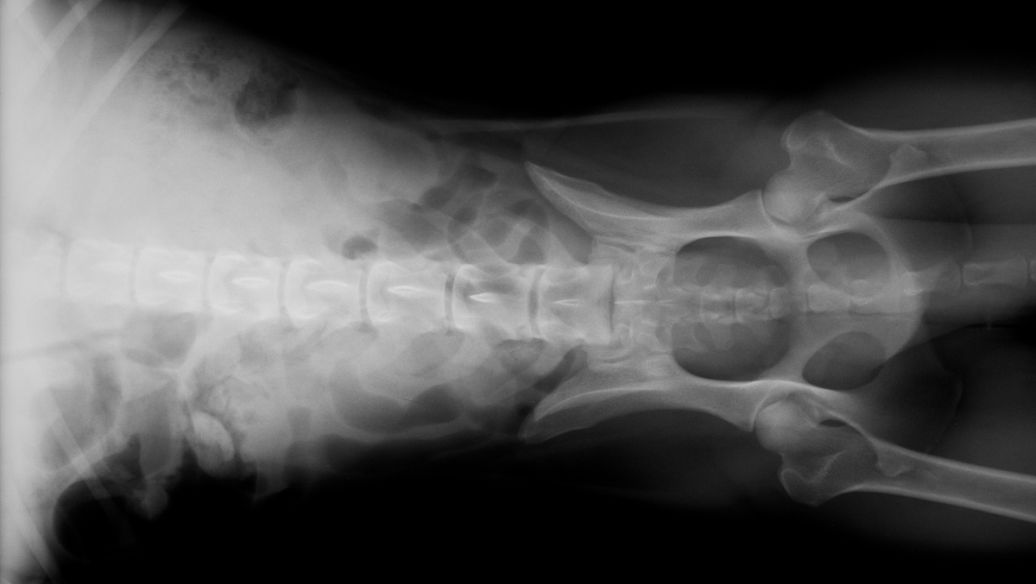

Poboljšanje stabilnosti ortopedskih implantata

Stabilnost ortopedskih implantata direktno određuje hiruršku prognozu. Osteoporoza i srodni faktori smanjuju integraciju kosti i implantata, predisponirajući za komplikacije kao što su labavljenje i migracija. Promoviše formiranje kosti oko implantata, poboljšava oseointegraciju i produžava životni vijek implantata. Aktivirajući osteoblaste, ubrzava sintezu koštanog matriksa i mineralizaciju na interfejsu implantata, formirajući stabilnu vezu kost-implantat i smanjujući gubitak peri{3}}implantatne kosti.